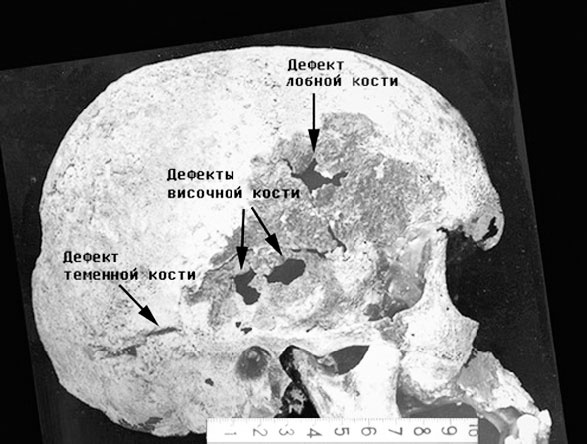

Ходили слухи об этом и в социал-демократических кругах. Некто Антон Горемыка писал: «От удара у него образовался на голове нарост, который до сих пор причиняет ему великие мучения, так что он часто страдает головными болями, доводящими его почти до бешенства. Правда, впоследствии проф. Павлову благодаря удачной операции удалось устранить нарост». [303] Собственно, именно в этой книжке, изданной в 1906 г. в Лондоне, впервые прозвучала информация об операции. В своей крайней форме слухи о последствиях ранения в Японии представлены в книге В. П. Обнинского: «Хотя, по-видимому, сотрясение мозга не последовало, но в черепной кости, слегка треснувшей от удара, началось разращение костного вещества. Процесс шел в обе стороны, и теперь Николай всегда испытывал в левой половине мозга давление, которое должно отразиться и на психических функциях. Продолжаясь годами, такой болевой эффект приводит к основательному расстройству или, во всяком случае, изменению интеллекта и нарушает психическое равновесие». [304] Именно эти слухи активно муссировались в либеральной среде накануне революции. Общепризнанным фактом является то, что Николай II после этого эпизода негативно воспринимал все, что было связано с Японией. Следует добавить, что отсутствие костной мозоли, сформировавшейся на месте ранения Николая, на черепе «№ 4», стало одним из веских аргументов противников захоронения царских останков в усыпальнице Петропавловского собора в 1998 г. Во время судебно-медицинской экспертизы, проводившейся Республиканским центром судебно-медицинской экспертизы Российской Федерации, этот вопрос был выделен особым пунктом. В официальной справке было зафиксировано, что «при условии получения повреждений, описанных в медицинском акте 1891 г., такие повреждения носили поверхностный характер и не могли сохраниться на черепе из-за того, что верхний слой черепа № 4 подвергся разрушению в результате неблагоприятных условий (воздействие серной кислоты, влаги и др.)». [305] ![]() Фото 1 Впоследствии полученные архивные документы позволили уточнить ряд важных позиций, связанных с расположением ран на голове Николая II. Как пишет судебно-медицинский эксперт С. А. Никитин, «все имевшиеся на нём повреждения были давно и подробно описаны: и разрушение наружной костной пластинки на всей поверхности черепа, и сквозные дефекты в наиболее тонких частях правой височной кости, и сквозной дефект правой половины лобной кости вблизи венечного шва, и поверхностный полосовидный дефект правой теменной кости позади наружного слухового отверстия» (см. фото 1). Образование этих повреждений правильно было объяснено воздействием сильнейшего химического реагента – концентрированной серной кислоты (кстати, изготовленной в Японии). Правда, образование дефекта правой теменной кости не было объяснено никак. Никто из экспертов, включая автора данной статьи, не подумал тогда о том, почему серная кислота, помимо воздействия на всю поверхность черепа, на лобную кость действовала столь локально?!. Ведь никакой ямки или анатомического истончения в этой части лобной кости нет… И откуда взялся этот полосовидный дефект теменной кости? И относительно недавно с автором произошло то, что определяется тезисом «большое видится издалека». Предельно ясным стало: истончение лобной кости у Николая II здесь было! И образовалось оно на месте первого удара японского меча. ![]() Фото 2 ![]() Фото 3 ![]() Фото 4 Отсюда, из «лобно-теменной» раны, доктор В. Барятинский [306] и извлек 12 мая 1891 г. тот самый осколок наружной костной пластинки, обнаживший губчатый слой (см. фото 2). И именно здесь серная кислота «проела» кость насквозь. Расположение и длина имеющегося дефекта лобной кости точно соответствуют расположению и длине извлечённого осколка, а полосовидный дефект теменной кости по уровню точно соответствует ране на краю ушной раковины (см. фото 3). Кроме того, стала понятна и наиболее вероятная последовательность причинения ран. Первым ударом меча была образована «лобно-теменная» рана, и цесаревич рефлекторно закрыл её кистью правой руки. В результате второго удара одномоментно на одной линии образовались три раны: «Затылочно-теменная, на краю правой ушной раковины и тыле правой кисти между указательным и большим пальцами (см. фото 4). Полагаю, что третьим ударом меча японец намеревался отрубить Николаю Александровичу голову». [307] Как повели себя врачи после отречения Николая II в марте 1917 г